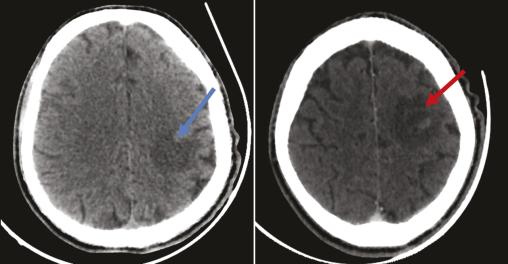

Un homme âgé de 51 ans, sans antécédents particuliers, a depuis deux semaines une hémiplégie droite et une dysarthrie évoluant dans un contexte d’apyrexie et d’altération de l’état général. À l’examen clinique, le patient, conscient, est stable sur le plan hémodynamique et respiratoire ; l’examen neurologique objective un déficit moteur de l’hémicorps droit. Les constantes sont les suivantes : température à 37,3 °C, pression artérielle de 125/75 mmHg, indice de masse corporelle (IMC) de 18,6 kg/m2. Le bilan biologique initial (hémogramme et protéine C-réactive) est normal. Le patient bénéficie en urgence d’une tomodensitométrie (TDM) cérébrale sans et avec injection du produit de contraste montrant des plages hypodenses éparses non systématisées avec prise de contraste annulaire après injection du produit de contraste (fig. 1 ). Par la suite, une imagerie par résonance magnétique (IRM) cérébrale caractérise ces multiples lésions parenchymateuses cérébrales sus- et sous-tentorielles en hypersignal T1, hypersignal T2 hétérogène, en hypersignal et Flair, avec une restriction sur la diffusion, se rehaussant en cible excentrée « target sign », avec œdème périlésionnel (fig. 2 ). Face à cet aspect radiologique, le diagnostic de toxoplasmose cérébrale est évoqué. Puis une sérologie toxoplasmique et au virus de l’immunodéficience humaine (VIH) se révèle positive, avec un taux de CD4 de 89 cellules/mm3. Le patient est traité par un antiparasitaire (pyriméthamine avec acide folinique) associé à une trithérapie antirétrovirale. Malgré une prise en charge rapide, l’évolution est marquée par une aggravation du tableau clinique, avec installation de troubles de la conscience ayant conduit au décès.

La toxoplasmose cérébrale est une infection parasitaire du système nerveux central par un protozoaire nommé Toxoplasma gondii. Cette infection concerne les patients immunodéprimés, notamment ceux infectés par le VIH.1 La toxoplasmose peut d’ailleurs être révélatrice de cette infection.2 Le tableau clinique est variable ; tout signe neurologique chez un patient atteint du VIH doit donc faire suspecter une toxoplasmose cérébrale.2 L’imagerie en coupe (TDM et IRM) joue un rôle important dans la démarche diagnostique en montrant classiquement des lésions multifocales de localisation variable, réalisant un effet de masse sur le parenchyme cérébral. Après injection, les lésions se rehaussent en périphérie en prenant parfois un aspect classique de « cible excentrée ».3 L’effet de masse peut entraîner un engagement sous-falcoriel en cas de lésions hémisphériques ou une hydrocéphalie obstructive.3 La confirmation du diagnostic est biologique.2 Le traitement est anti-infectieux, visant Toxoplasma gondii et le VIH, et symptomatique contre l’hypertension intracrânienne.1 Le traitement antiparasitaire est généralement fondé sur la pyriméthamine en association avec un médicament d’appoint comme la sulfadiazine ou la clindamycine ; l’acide folinique est prescrit en même temps que la pyriméthamine, pour prévenir les carences en folates. Chez les patients atteints du syndrome d’immunodéficience acquise (sida), le traitement de la toxoplasmose cérébrale doit être associé à une thérapie antirétrovirale efficace pour contrôler la charge virale et restaurer la fonction immunitaire.1 Le traitement de l’entourage n’est pas nécessaire. Il est recommandé de tester les partenaires sexuels des personnes vivant avec le VIH pour prévenir la transmission du virus.